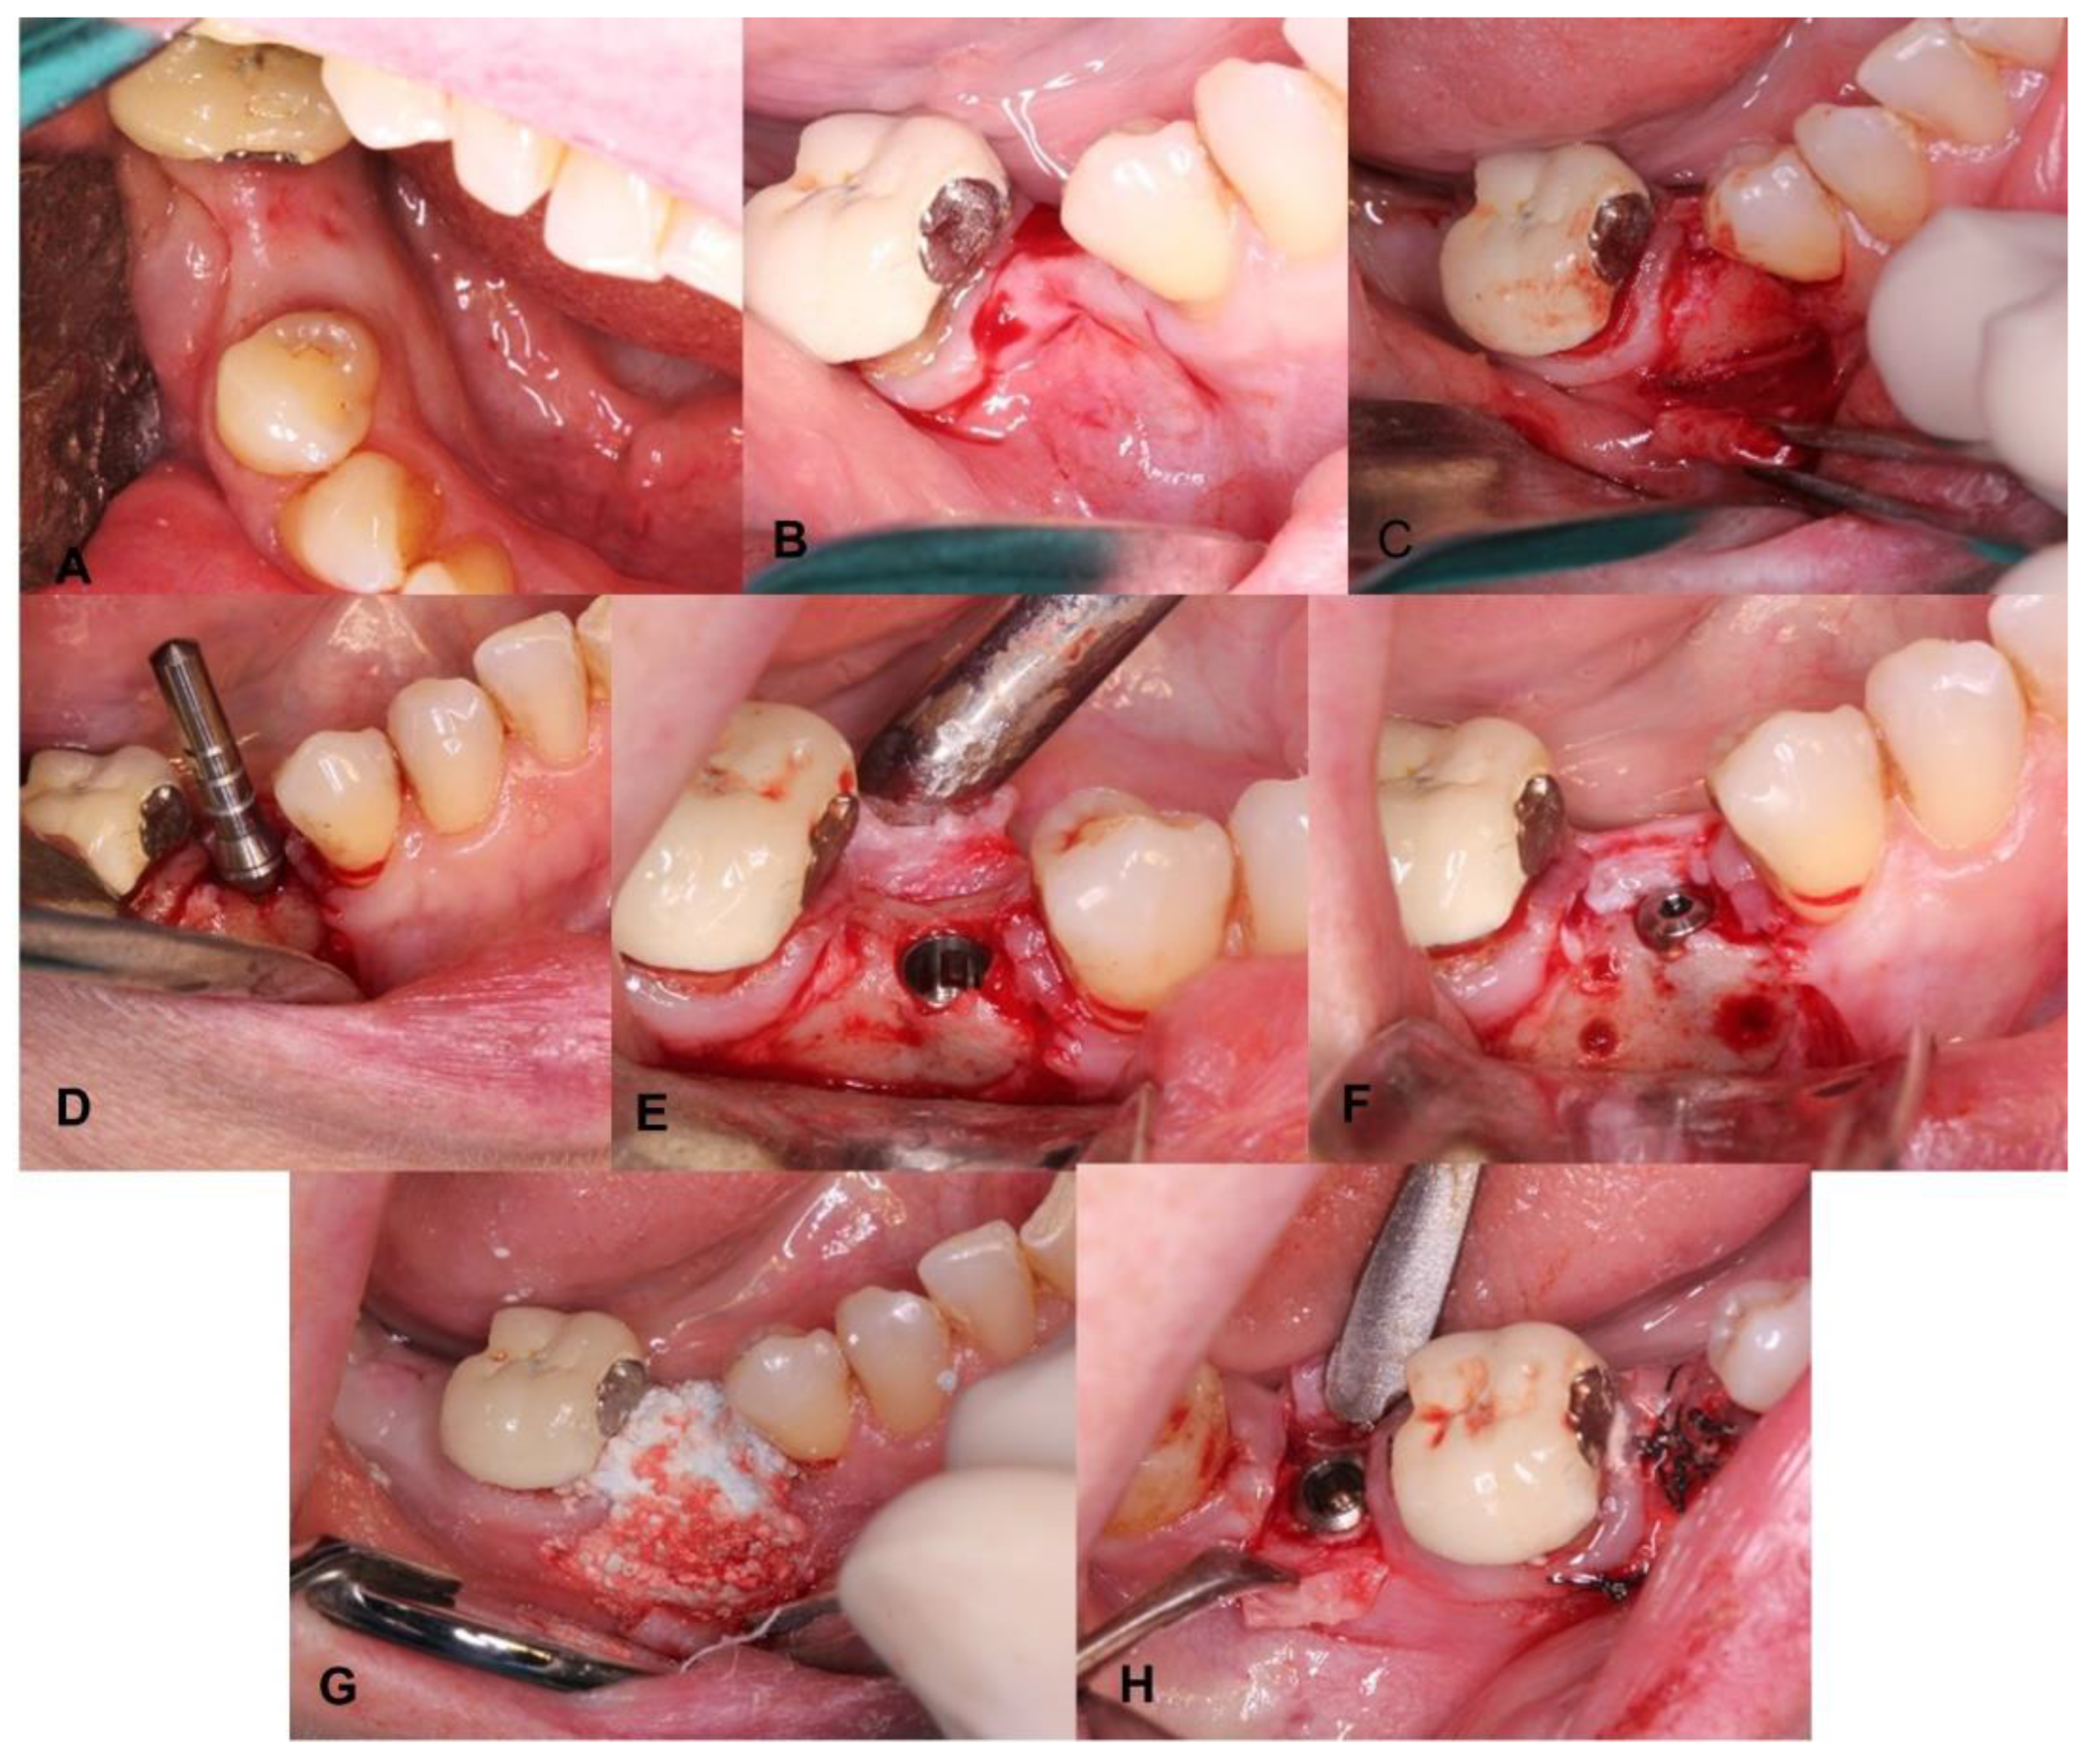

4. Clinical Cases

4.1. Patient No. 1

4.2. Patient No. 2

4.3. Patient No. 3

4.4. Patient No.4

4.5. Patient No.5

4.6. Patient No.6